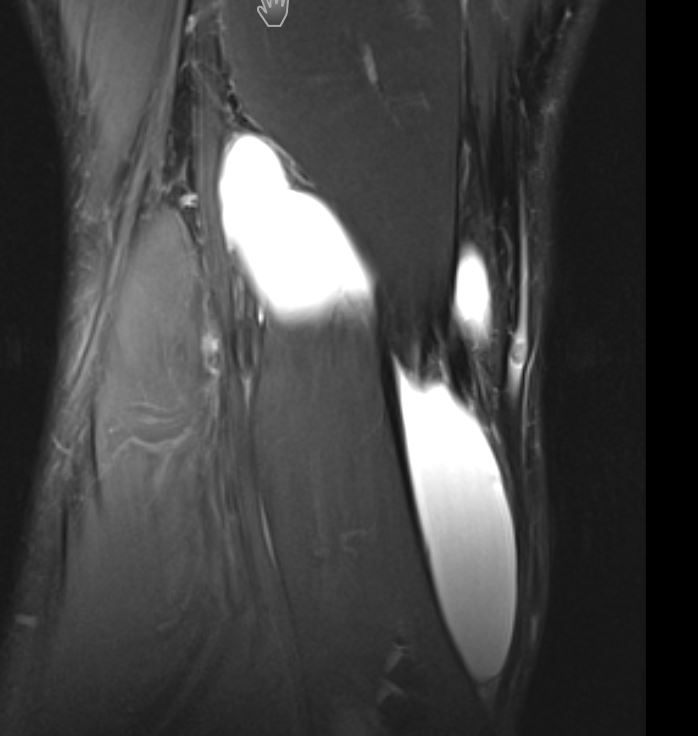

Ach ja...im MRT...die Bakerzyte...größer denn je:

Bakerzyste1.JPGBakerzyyste2 2.JPGZyste 3.JPG